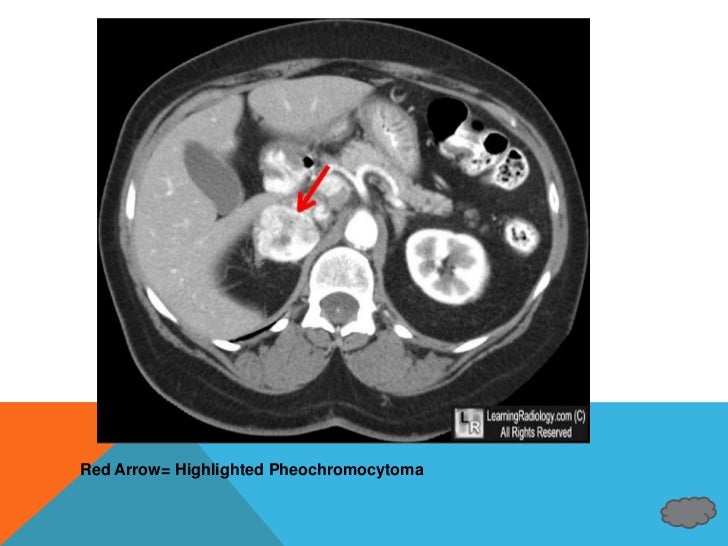

From www.slideshare.net